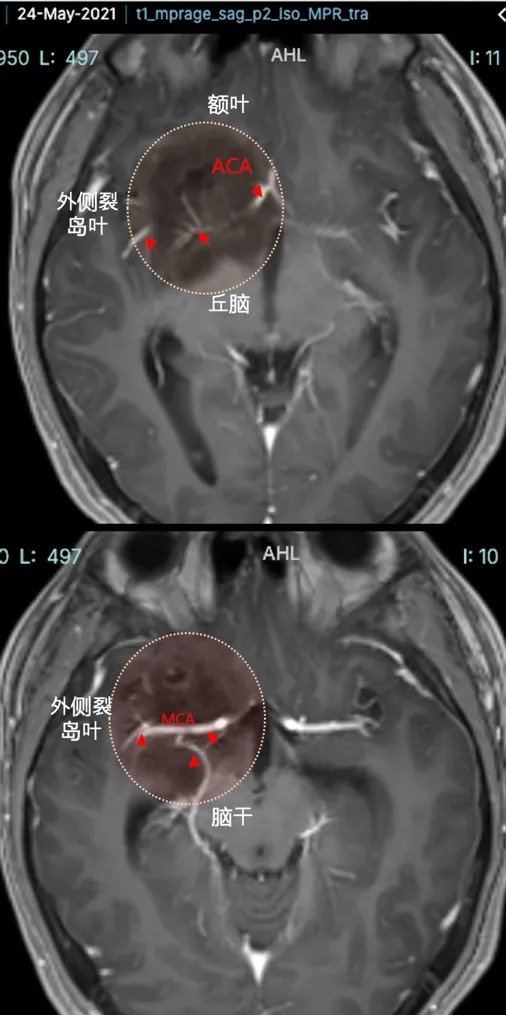

小磊术前MRI影像显示右额、颞、基底节区、侧脑室前角区巨大占位(胶质瘤),压迫丘脑,从右额白质延伸到岛叶和基底节前部,部分浸润丘脑和右下丘脑,并向颅内延伸到前连合和室间孔。

肿瘤血管丰富包裹大脑前动脉、大脑中动脉及其分支等。

巴教授手术情况:巴教授近全切肿瘤,手术过程中未出现并发症。手术做完当天,小磊成功拔管并转入ICU。术后第2天,意识清醒,无新发神经系统损伤。转回神经外科普通病房,并在康复治疗师的指导下开始活动。小磊很快就开始独立行走。

术后第12天,小磊就出院了,出院时他与手术前的状态一样,意识清楚、反应灵敏、定向准确、无新的神经功能障碍。

术后病理:DNET,全切后预后良好

术后3年复查无复发